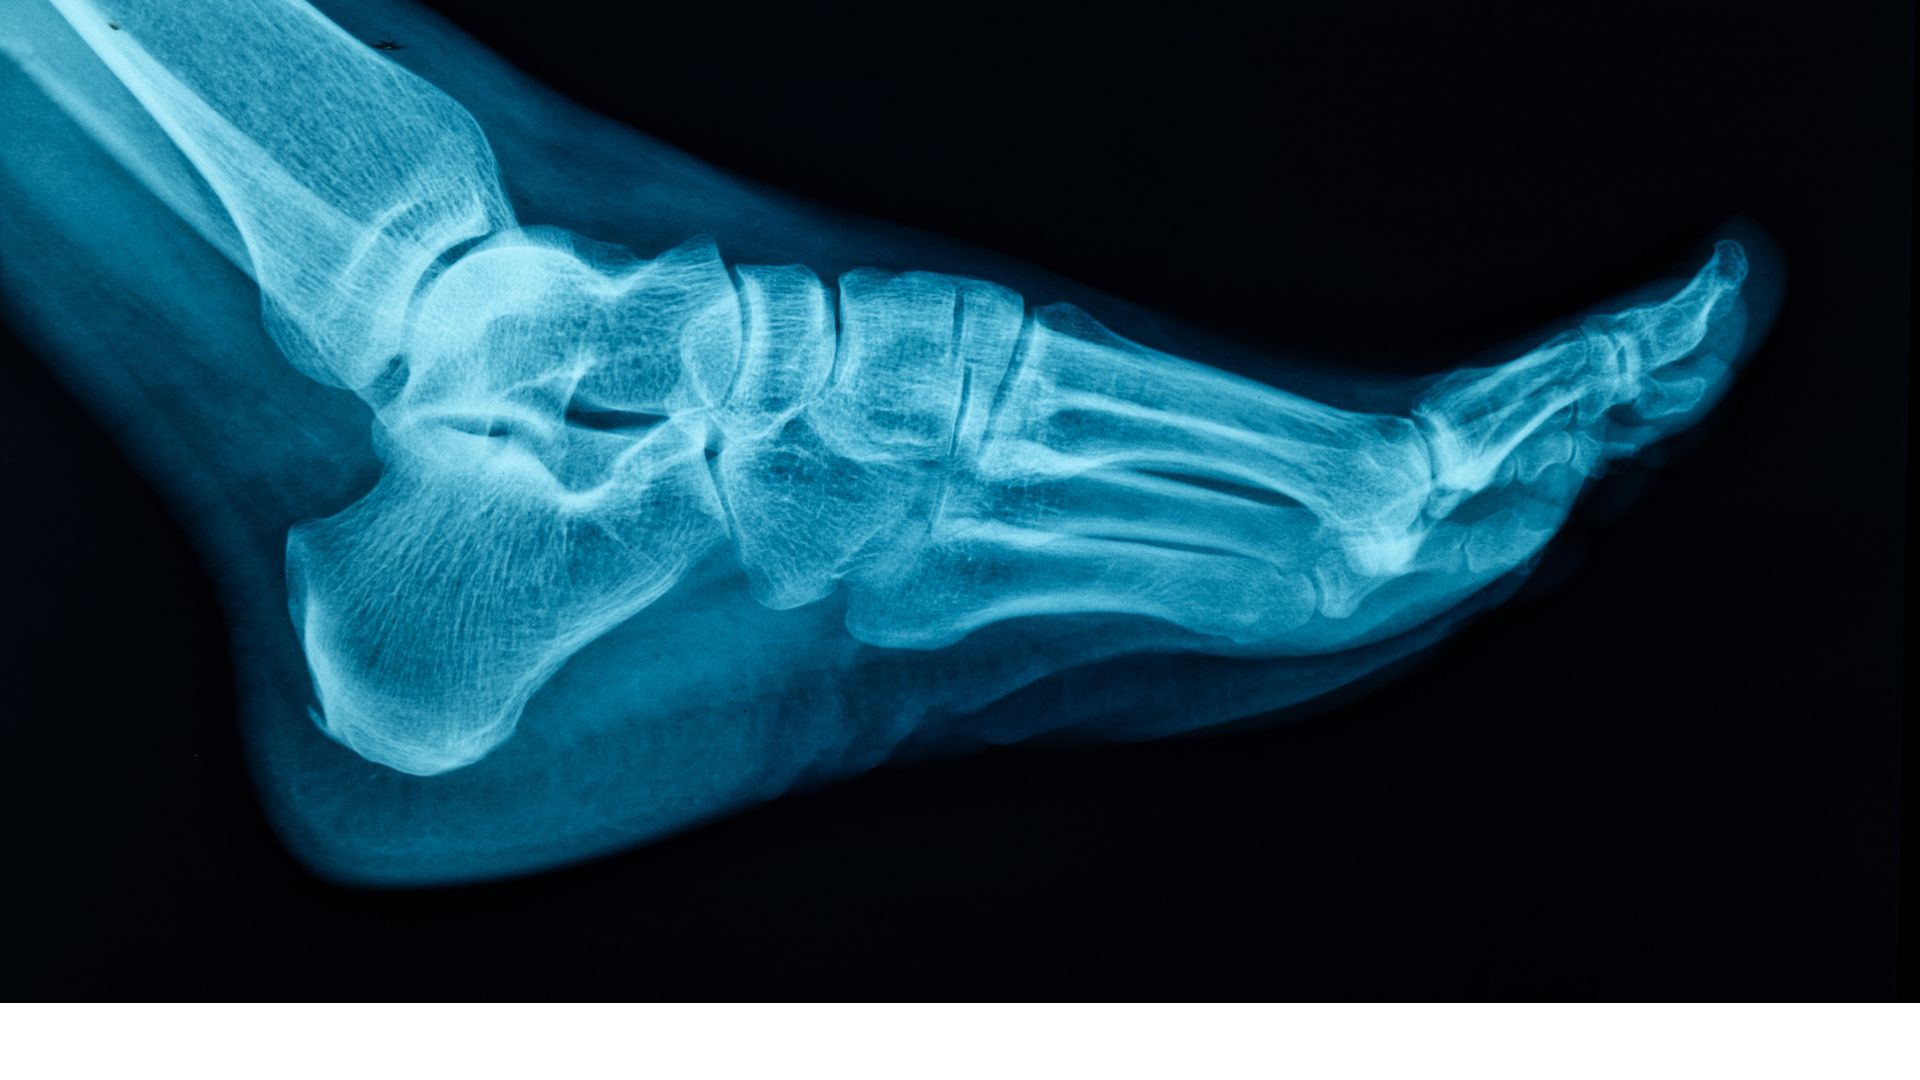

Como proteger seus pés: ortopedista alerta para riscos de traumas e desgaste natural

Descubra as principais medidas de prevenção contra lesões, o impacto dos calçados na sua coluna e como as novas tecnologias cirúrgicas ajudam na recuperação